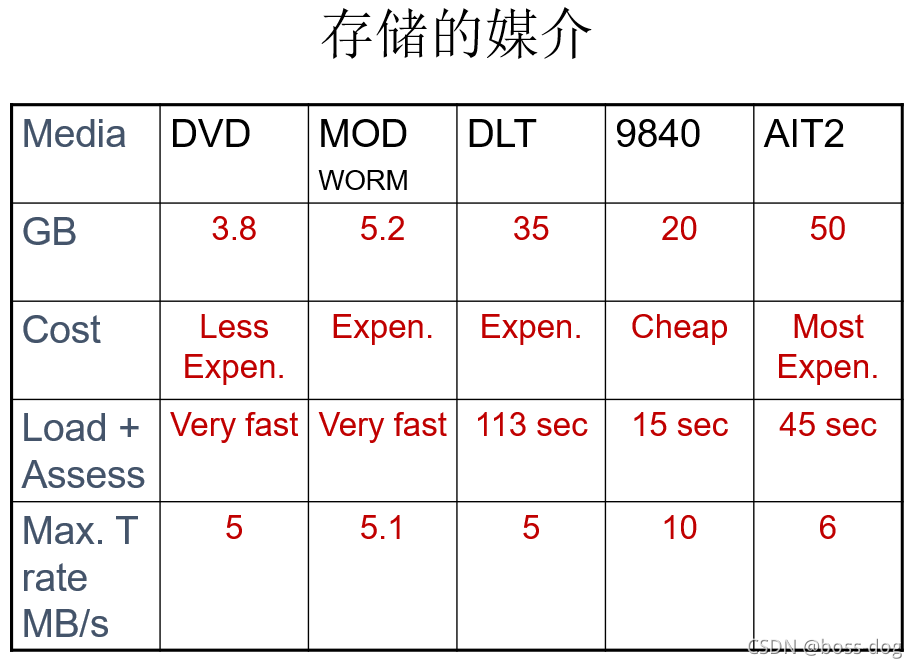

7.PACS

A:存档、在线、近线、离线